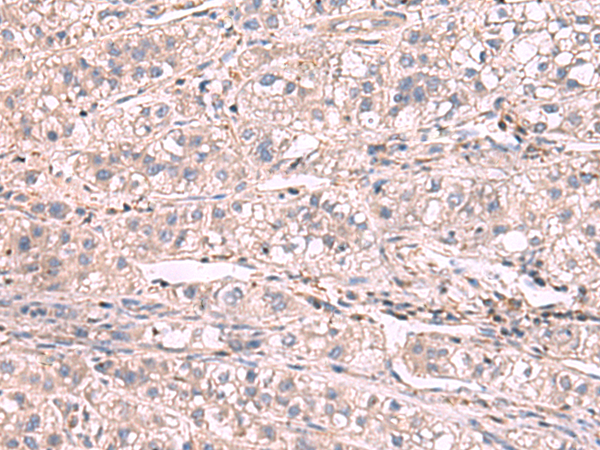

(Immunohistochemistry of paraffin-embedded Human liver cancer tissue using KCNIP1 Polyclonal Antibody at dilution of 1:60(×200))